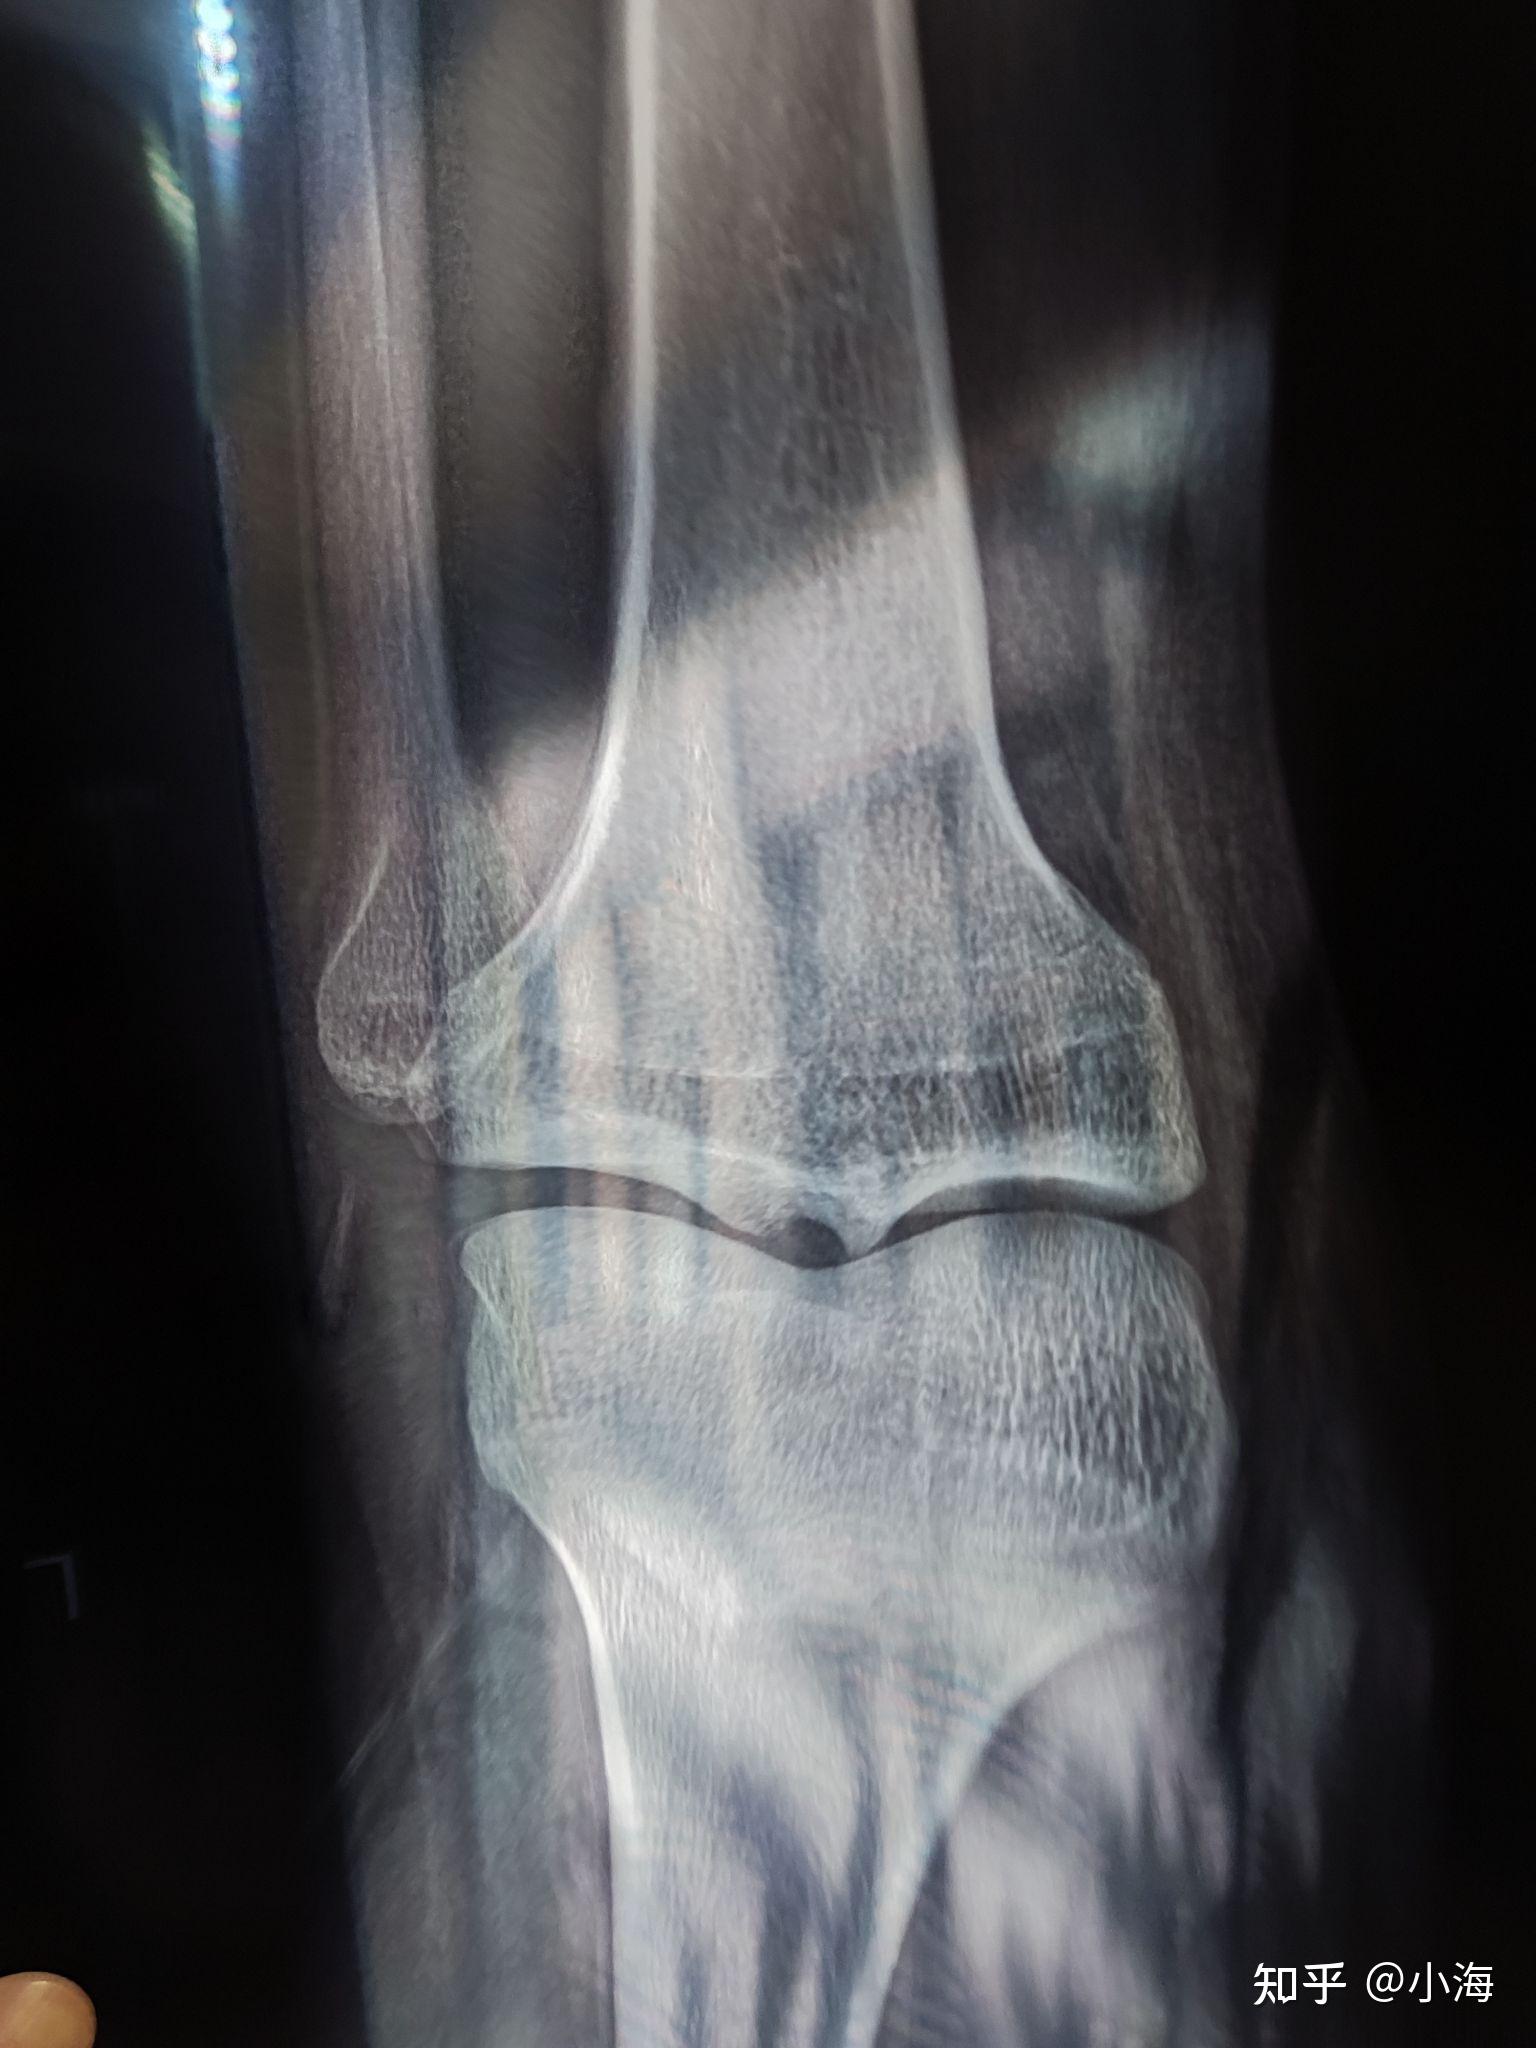

骨骺线算闭合了吗?